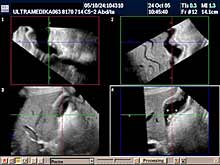

Posebni pregledi:

- Fokalne promene jetre, pankreasa i ostalih parenhimatoznih organa (3D

Sono CT procena i procena vaskularizacije sa Broad band-CD i PD i 3D

CPA modom).

- 3D Sono CT i 3D CPA promena na tankom i debelom crevu

- 3D Sono CT želudca i intra abdominalnog dela jednjaka (hidrograstična

sonografija)

- 3D Sono CT debelog creva (HIDROKOLON).